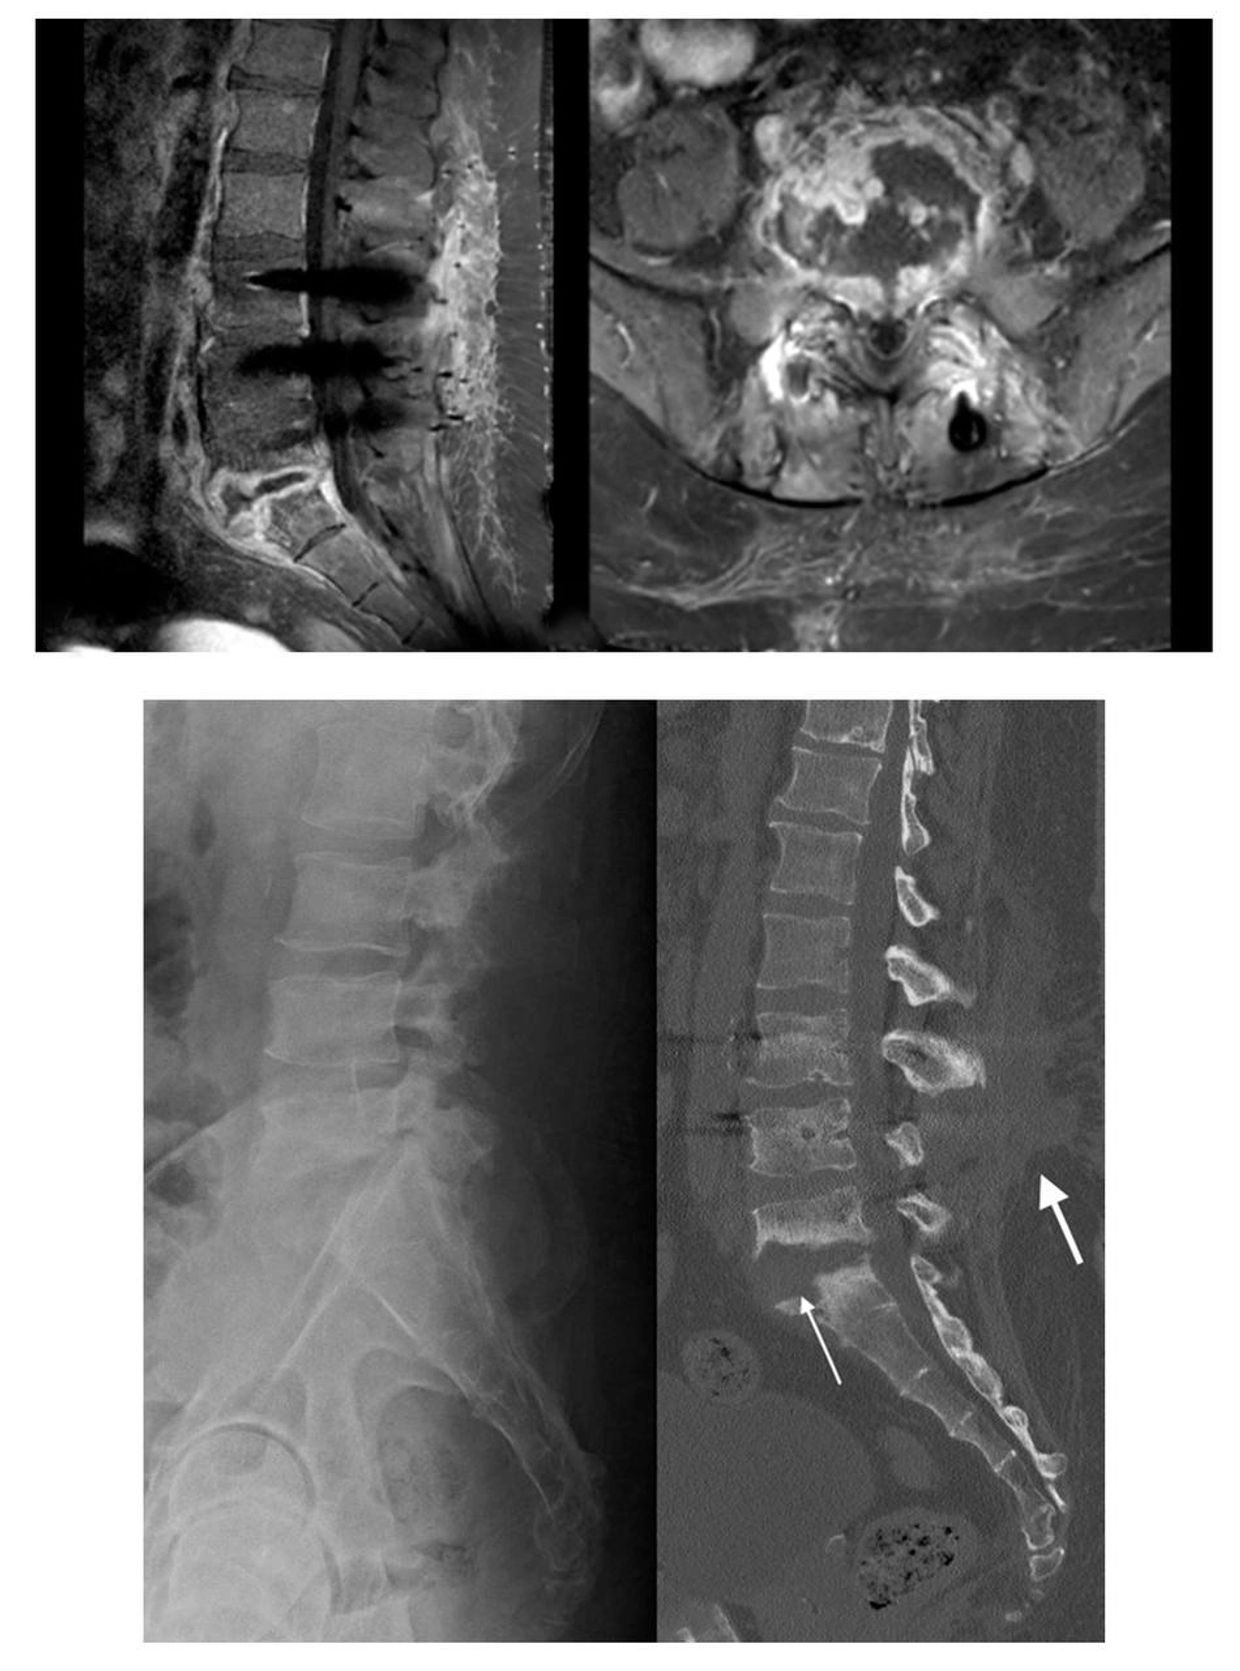

Diagnosis

• Detailed medical history and physical examination• Blood tests to identify infection markers• Imaging studies such as MRI and CT scans to detect the extent of infection• Sometimes biopsy or fluid sampling to identify the exact organism